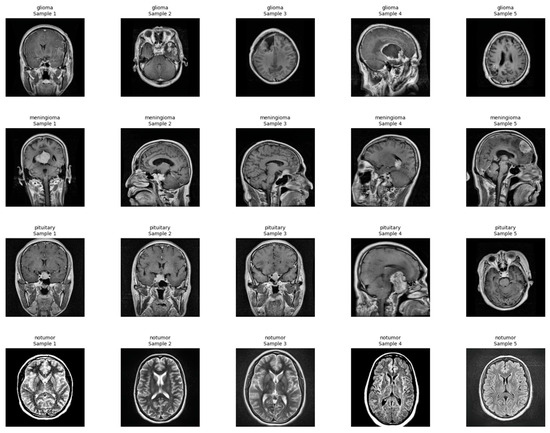

For better visualization of the dataset structure, a few representative training, validation, and test samples were plotted by randomly extracting slices from the 3D volumes. Segmentation masks of the TC, WT, and ET subregions over the images were coded using red, green, and blue color maps, respectively. A few example images illustrating the anatomical variability and tumor heterogeneity of the dataset are provided in Figure 2.

Explainability of the 3D segmentation model was also assessed using slice-level over-lays that were obtained by Gaussian-smoothing the WT and ET segmentation masks. Representative images are presented in Figure 13, Figure 14 and Figure 15, demonstrating both segmentation quality and spatial explainability.

In Figure 13, the segmentation output successfully localizes the tumor region. The corresponding explainability overlay displays brighter reddish intensities concentrated near the inferior and lateral tumor margins. These brighter areas represent regions where the segmentation model exhibited the highest voxel-wise activation strength (post-sigmoid output near threshold). The alignment between the segmentation mask and the explainability overlay indicates that the model consistently identified these tumor regions as contributing strongly to its segmentation decision.

In Figure 14, we can once more observe the same pattern, which strongly resembles previous findings, with the segmentation map cleanly delineating the bulk of the tumor, defining its presence in explicit terms. Additionally, the explainability overlay performs a crucial role by bringing to light the high-response areas that are observed along the border core of the tumor itself. The areas marked in the brightest shade of red once again indicate voxel clusters that are associated with the greatest degree of model confidence in terms of describing the tumor. The adjacent brain parenchyma is largely dark in the attribution map, indicating a low saliency signal and thereby confirming the model’s capability to spatially limit its predictive confidence to the tumor boundary. Low attribution outside the edge of the lesion is an indicator that the model is specific and can suppress false positives in the non-pathological tissue neighboring the lesion.

In Figure 15, the overlay highlighting explainability demonstrates a drastically sharper and more accurate localization, with clusters that are vivid yellowish-red and closely placed near the center of the tumor. This serves to reinforce that the model is consistently focusing its activation on the pertinent subregions of the tumor in different patients, pointing to a high degree of reliability in its operation. Most notable is that, even though there is an outer segmentation mask that looks overall rough and a bit noisy as a result of the nature of voxel-wise thresholding, the heatmaps relating to explainability offer well-refined visual indications. These indications specifically demonstrate the zones that the model has most confidently segmented, thus providing us with a better grasp of its analytical properties.

Despite the fact that the raw segmentation boundaries at times seem irregular and rough because of the inherent characteristics that come with thresholding the outputs of probabilistic models, the overlays that are used to provide explainability serve to add and elaborate on the interpretation of the results. This is due to the fact that by accentuating specific areas where the model indicates high confidence in its identification of tumors, the overlays provide further insights besides imparting visual confidence that adds further conviction to clinicians when reviewing and assessing the results that are generated by automated segmentation techniques.

Figure 2. Representative 3D MRI samples with segmentation overlays for TC, WT, and ET.